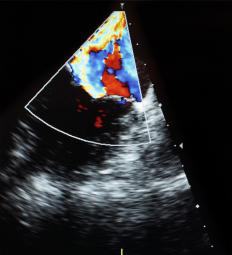

医疗领域使用数字多普勒来拯救生命。在这种用途中,电磁波AV 可以让医生在不切开皮肤的情况下直观地了解身体内部。这些波可以创建体内器官或异物的二维 (2D) 或三维 (3D) 视图。妊娠超声检查使用 2D 和 3D 多普勒为父母和产科医生提供婴儿的第一张图片。